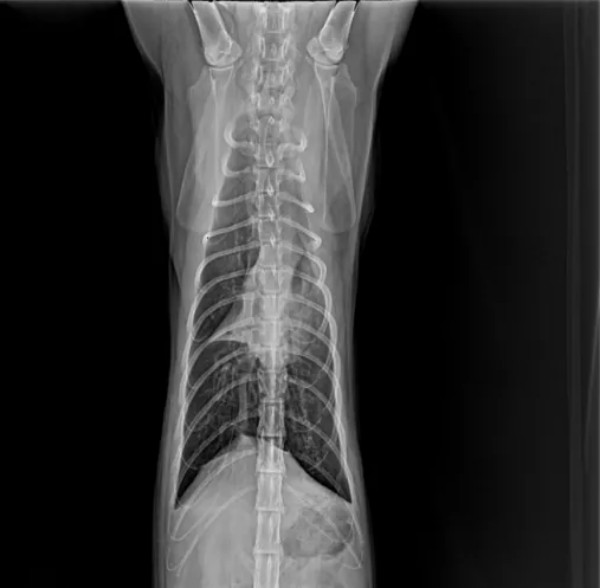

一、引言 猫咪肺炎根据发病快慢有急性肺炎和慢性肺炎之分,猫咪急性肺炎的症状主要表现为突然发高烧、呼吸不畅、腹泻等;慢性肺炎通常表现为长时间咳嗽、有痰、食欲下降、精神不振、呼吸不畅等。 猫咪如果患上肺炎就需要及时治疗,否则很容易引发相关的并发症,威胁到猫咪的性命。肺炎常见原因:感染性(细菌感染、病毒感染、寄生虫感染)、非感染性(吸入性、异物性、过敏性、继发性等) 二、病例基本信息及病史 2.1基本信息 一只缅因猫,雄性未绝育,体重5.85Kg,免疫不全,驱虫正常。 2.2主诉疾病史 最近几天精神良好,就诊当天发蔫,食欲不振,偶尔咳嗽,打喷嚏,4天前家里新领养一只小猫。既往病史 :疱疹病毒,杯状病毒,伯氏杆菌。 三、检查及化验项目和结果 3.1血常规检查 3.2 血清样淀粉蛋白检查 3.3生化检查 3.4fNT-PrOBNP猫N端脑钠肽前体 3.5影像学检查 四、诊断结果 肺炎;肺叶实变 五、治疗方案及预后 5.1经验性治疗 克维舒:一天两次,一次2ml; PO 麻杏石甘汤:一天两次,一5ml;PO 5.2复诊 用药2周后复诊,整体情况好转,咳嗽明显好转,喷嚏减少,分泌物减少,食欲恢复。炎症指标明显好转,肺部影像明显好转。 5.3复查结果 5.3.1血常规检查 5.3.2 血清样淀粉蛋白检查 5.3.3影像学检查 图4胸腔侧位 5.4治疗转归 巩固治疗:克维舒 一天两次,一次2ml,PO 该动物目前恢复良好,状态稳定,直至投稿前回访,一切正常。肺实变位置需密切监测,病变位置可能伴随终身。 六、讨论及小结 猫咪肺炎的发病原因一般是由细菌、真菌、病毒等微生物感染引起。甚至像寄生虫移行、外力因素、吸入性因素、机体免疫力下降等,都可诱发肺炎。严重的肺炎可能会导致肺部渗出增多、肺水肿等,引起急性呼吸困难。猫咪的肺炎在初期通常很隐蔽,甚至没有太大的症状和表现,发病非常突然,以精神沉郁、厌食、急性的呼吸困难为主,送医不及时容易耽误病情。该病例因为发现较早,治疗后整体预后良好。 肺炎的诊断:咳嗽的犬猫出现发烧、嗜睡、食欲不振或呼吸急促症状时应进行全面检查,血细胞计数和胸部X线检查评估是否存在肺炎。根据结果怀疑细菌性或支持细菌性肺炎的诊断时,应采集气管,支气管内或支气管肺泡灌洗进行细胞学检查,需氧培养、药敏实验和支原体培养。该病例未做相关检查,主人要求先对症治疗。 在开始抗菌治疗之前,都应该建议宠主进行培养和药敏实验,前提时动物状况足够稳定。但所有治疗检查应和宠主充分沟通,特别时需要长时间或管理时间比较长的病例,在治疗时应制定个性化治疗方案,将宠物主人的意愿,配合程度,可自由支配时间,动物配合程度都应纳入考量,从而提高治疗质量,护理质量以及医从性。 该病例综合考虑最终抗菌药物选用克维舒,一方面该病例未做培养及药敏,作为临床医生应选择一线广谱抗菌药物,安全性高的药物,从而提高治愈率。另一方面考虑到动物主人时间以及该猫吃药困难,克维舒易口服,操作简单,很大程度上减少猫咪应激,节省主人时间,同时增加了宠主成就感。从而提高了治愈率,也增加了宠主对医生的信任,所以最终选择了克维舒。 七、参考文献 1.Sykes, J. E. (2014).Feline lower respiratory tract disease. In J. E. Sykes (Ed.), Canine and Feline Infectious Diseases (pp. 161-173). 2.Reinero, C. R. (2011).Feline Asthma and Bronchopulmonary Disease. Veterinary Clinics of North America: Small Animal Practice, 41(2), 191–211. 3.Lappin, M. R., Blondeau, J., Boothe, D., Breitschwerdt, E. B., Guardabassi, L., Lloyd, D. H., ... & Sykes, J. E. (2017).Antimicrobial use Guidelines for Treatment of Respiratory Tract Disease in Dogs and Cats: Antimicrobial Guidelines Working Group of the International Society for Companion Animal Infectious Diseases. Journal of Veterinary Internal Medicine, 31(2), 279–294. 4.夏兆飞,陈艳云,王姜维主译.小动物内科学(第5版) [M].中国农业大学出版社,2019,11:297-300.